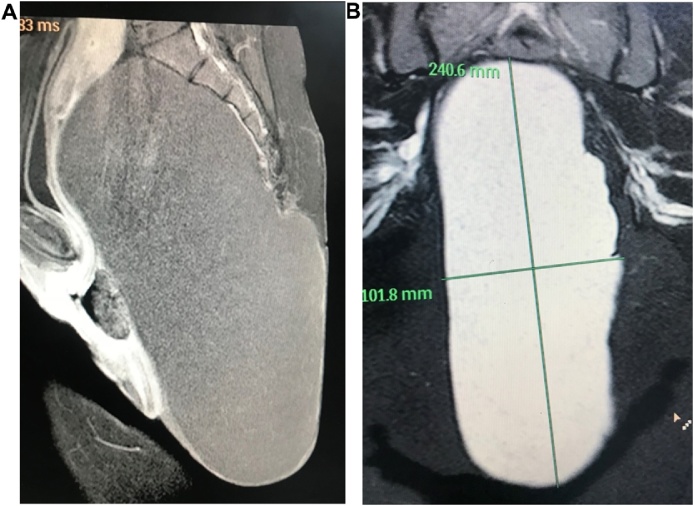

Magnetic resonance imaging studies (MRI) showed a well-defined encapsulated mass of 25, 15, 10 cm size. The mass was filling the presacral space, extending up the pelvis and down posterior to the rectum and anal canal compressing both and the urinary bladder with a huge extra corporal extension Fig. 2(A and B).

Fig. 2.

(A): MRI of the pelvis showing cyst filled with faint calcifications with clear margins except over the lower coccyx compressing the pelvic structures anteriorly and superiorly. (B): MRI showing dimensions of the cyst and relations with pelvic structures.

It appeared hypo-intense in T1 weighted images with faint calcification spots while it showed hyper intensity in T2 imaging with clear surrounding boundaries except for a close relation to the coccyx. There was no enhancement of the lesion and no invasion of the adjacent structures nor was bone erosions. MRI findings were interpreted as a Sacrococcygealteratoma, possibly originating from the coccyx. However, the differential diagnosis was going around other rare conditions as rectal duplication cysts, lipoma, liposarcoma, sacrococcygealchondromas and chordomas.